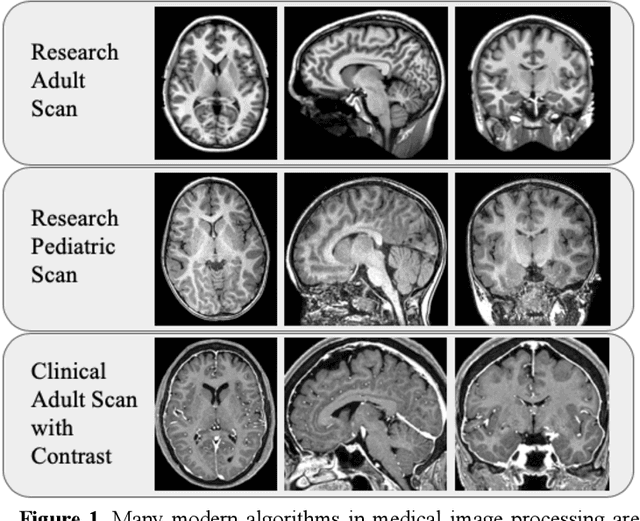

Abstract:Generalizability is an important problem in deep neural networks, especially in the context of the variability of data acquisition in clinical magnetic resonance imaging (MRI). Recently, the Spatially Localized Atlas Network Tiles (SLANT) approach has been shown to effectively segment whole brain non-contrast T1w MRI with 132 volumetric labels. Enhancing generalizability of SLANT would enable broader application of volumetric assessment in multi-site studies. Transfer learning (TL) is commonly used to update the neural network weights for local factors; yet, it is commonly recognized to risk degradation of performance on the original validation/test cohorts. Here, we explore TL by data augmentation to address these concerns in the context of adapting SLANT to anatomical variation and scanning protocol. We consider two datasets: First, we optimize for age with 30 T1w MRI of young children with manually corrected volumetric labels, and accuracy of automated segmentation defined relative to the manually provided truth. Second, we optimize for acquisition with 36 paired datasets of pre- and post-contrast clinically acquired T1w MRI, and accuracy of the post-contrast segmentations assessed relative to the pre-contrast automated assessment. For both studies, we augment the original TL step of SLANT with either only the new data or with both original and new data. Over baseline SLANT, both approaches yielded significantly improved performance (signed rank tests; pediatric: 0.89 vs. 0.82 DSC, p<0.001; contrast: 0.80 vs 0.76, p<0.001). The performance on the original test set decreased with the new-data only transfer learning approach, so data augmentation was superior to strict transfer learning.